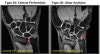

Type 1 tears are called traumatic tears. Falling on an outstretched hand and excessive arm rotation are the most common causes.

Type 2 TFCC tears are degenerative or chronic. They can occur over time and with age. The degenerative process wears the cartilage down over time. Some inflammatory disorders, such as rheumatoid arthritis or gout, may also contribute to Type 2 TFCC tears.

* Central : Poor vascularized(Healing potential minimal)

Arthroscopic debridement up to 2/3 of articular disc